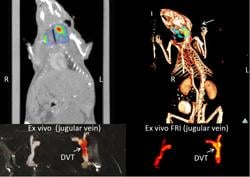

In conjunction with the new near-infrared fluorescence fibrin-targeted peptide, investigators were able to successfully detect fibrin-rich deep vein thrombosis with both intravital fluorescence microscopy and noninvasive fluorescence molecular tomography, which allows researchers to acquire information about tissues by analyzing how light is absorbed by and scattered from tissues. By coupling the fibrin peptide agent (EP-2104R) with rapidly emerging intravascular NIRF imaging, researchers now have the opportunity to study micro-thrombi on coronary artery plaques and coronary stents that are at especially high risk for thrombosis and vessel occlusion, the main cause of heart attacks. This could help clinicians predict potential heart attacks and other major cardiovascular events before it is too late, thus potentially saving the lives of patients.